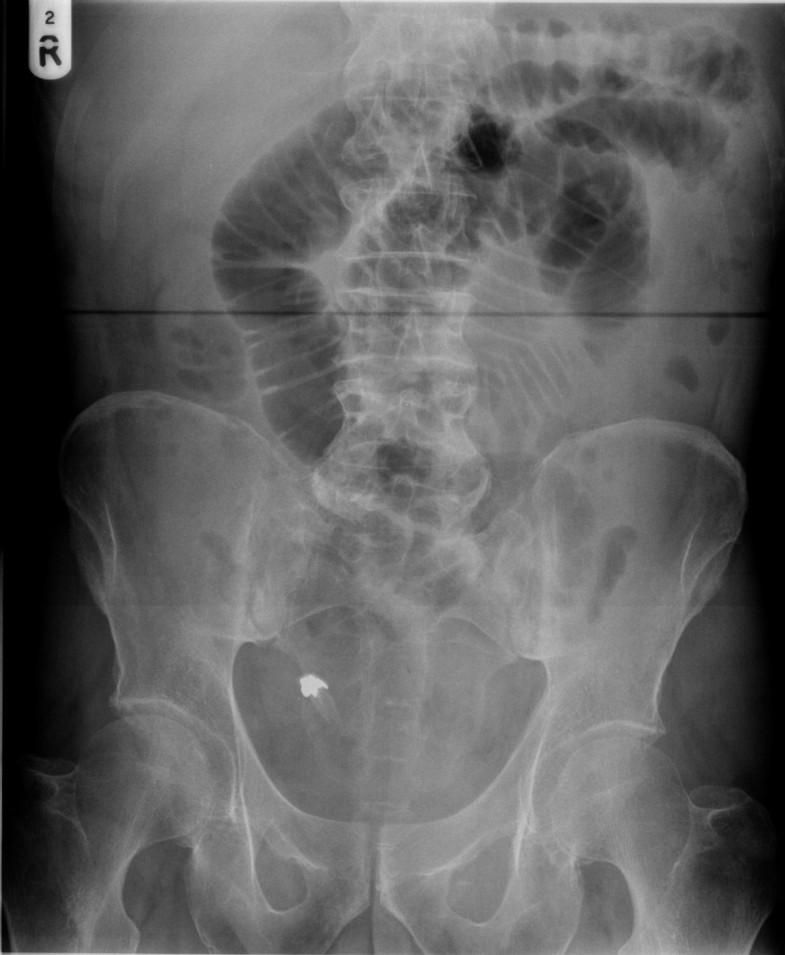

Dental Bur Swallowed . The case of a fractured scaler tip. Though it’s rare, accidental swallowing of dental instruments happens — and can cause some serious complications. These mishaps are by their very nature unexpected, and successful prevention and management are key to minimizing potential adverse consequences. An 84‐year‐old male with atrial fibrillation, hypertension, and type 2 diabetes mellitus was brought to the emergency room of our hospital. These tips will help walk you through. In oral healthcare, ingestion or aspiration of foreign objects are significant iatrogenic events. The accidental ingestion or aspiration of dental materials during treatment can be particularly troublesome. Most dental burs are sharp and dangerous and can puncture the digestive tract, if ingested. A new report highlights five cases that involved patients who swallowed or aspirated dental instruments.